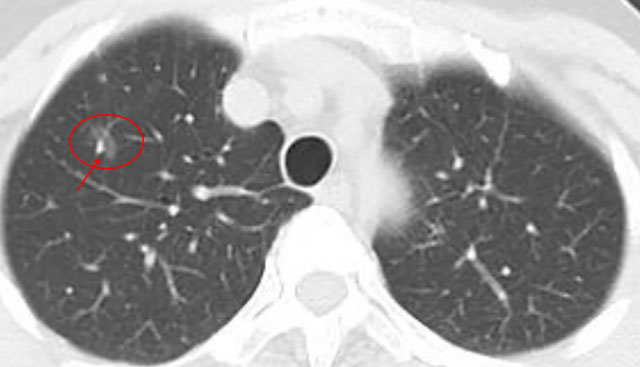

几年前,一位阿姨体检发现双肺多发10余个磨玻璃结节,最大位于右肺上叶,约9mm。当时判断:多为低风险,医生建议半年随访。

几年前影像展示与分析,5mm层厚、无薄层。

上图中红色圈原位癌可能性较大,尤其右肺上叶尖段二个结节,可见血管增粗及血管弯5mm层厚,无薄层重建;橙色圈多考虑不典型增生可能性大;黄色圈大概只是肺泡上皮增生;绿色圈考虑是良性的。